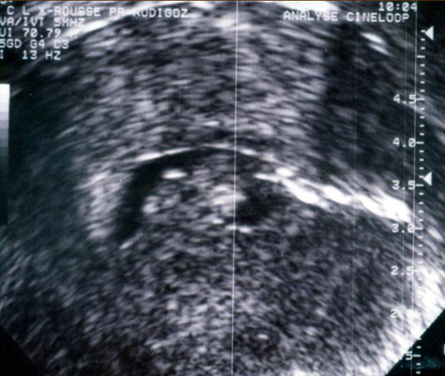

Hystérosonographie. Lésion endocavitaire hétérogène liée au tamoxifène